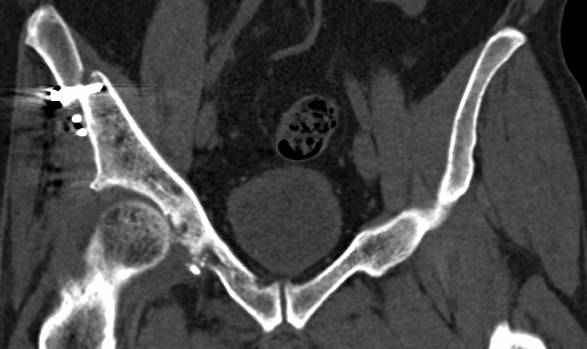

Re: перелом правой половины таза

высылаю дополнительно сканы.